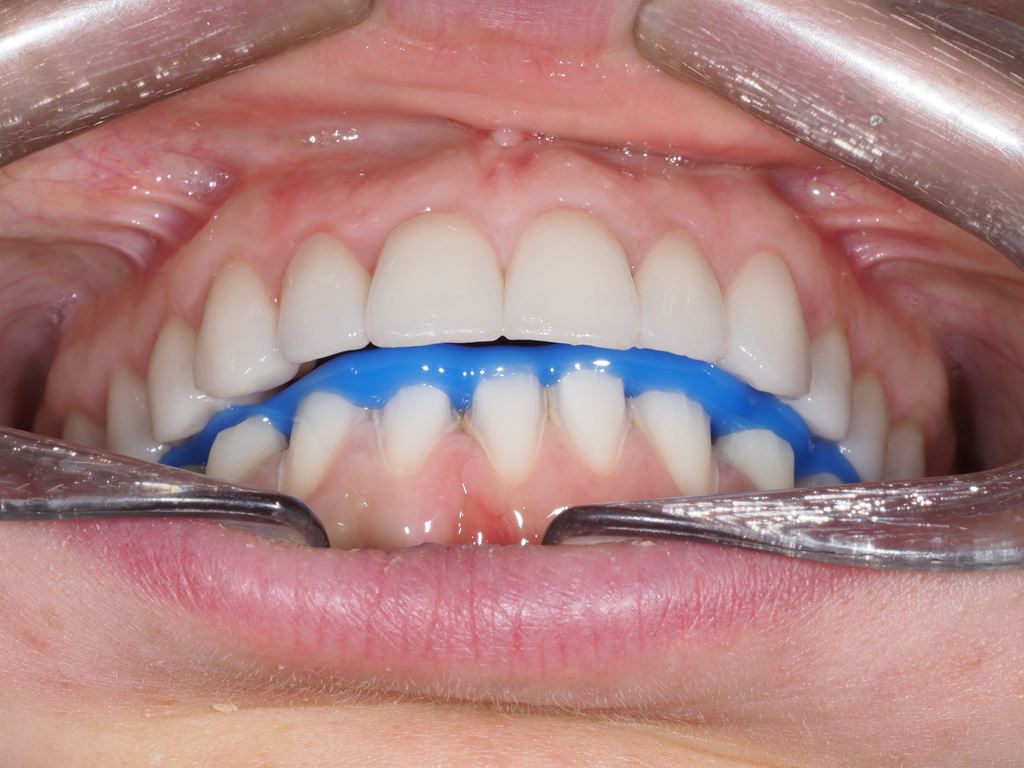

Wykonano także modele diagnostyczne zaartykulowane w relacji centralnej (RC), którą zarejestrowano ze względu na zwiększone napięcie mięśniowe z wykorzystaniem deprogramatora Koisa (ryc. 13-15), oraz zdjęcie pantomograficzne (ryc. 16) i cefalometryczne. Analiza modeli w RC wykazała przesunięcie żuchwy w kierunku doprzednim w stosunku do pozycji maksymalnego zaguzkowania i przedwczesne kontakty funkcjonalne na zębach bocznych, co tłumaczyło obecność odprysków szkliwa na brzegach siecznych górnych zębów (szczególnie wyraźne na zębie 12) (ryc. 14, 17). Na modelach wykonano studium funkcjonalne mające na celu określenie, w jaki sposób można odtworzyć prawidłową funkcję, tzn. uzyskać prawidłowy nagryz pionowy i poziomy oraz prowadzenie przednie (ryc. 18-20).

Następnie, po okresie stabilizacji i wstępnej korekcie okluzji, na podstawie analizy nowego kompletu zdjęć i modeli, wykonano woskowanie diagnostyczne oraz mock-up górnego łuku zębowego mający na celu potwierdzenie ostatecznego kształtu zębów i zakresu niezbędnego przygotowania chirurgicznego (ryc. 25-27).

Po 6 miesiącach od zabiegu chirurgicznego rozpoczęto leczenie protetyczne mające na celu odbudowę prawidłowej anatomii zębów i odtworzenie utraconej funkcji żucia. W pierwszym etapie zaplanowano rekonstrukcję górnego łuku zębowego, wzorując się na wcześniej wykonanym woskowaniu i mock-upie. Preparacja przez mock-up pozwala na minimalnie traumatyczne szlifowanie, co jest szczególnie istotne w przypadkach takich jak przedstawiony, gdy już doszło do znacznej utraty tkanek na powierzchniach żujących zębów bocznych (16) (ryc. 30). Przed wykonaniem docelowych rekonstrukcji ceramicznych sprawdzono wyfrezowany z żywicy akrylopolimerowej (PMMA) prototyp z jednocześnie założonym na dolny łuk zębowy mock-upem (ryc. 31).